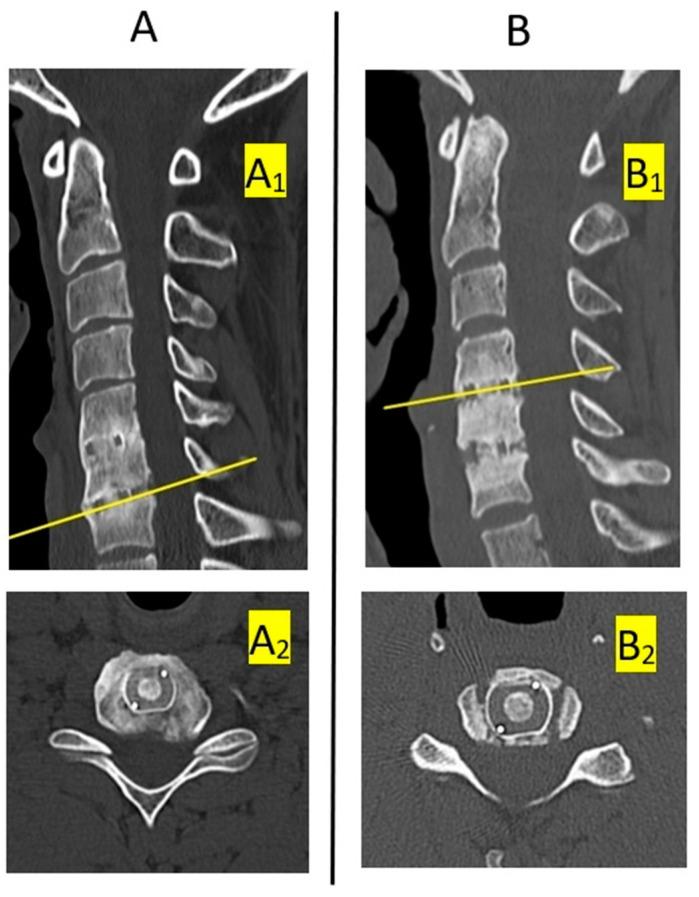

Most surgical procedures performed on account of degenerative disease of the cervical spine involve a discectomy and interbody fixation. Bone fusion at the implant placement site is evaluated post-operatively. It is agreed that computed tomography is the best modality for assessing bone union. We evaluated the results obtained with various methods based solely on conventional radiographs in the same group of patients and compared them with results obtained using a method that is a combination of CT and conventional radiography, which we considered the most precise and a reference method. We operated on a total of 170 disc spaces in a group of 104 patients. Fusion was evaluated at 12 months after surgery with five different and popular classifications based on conventional radiographs and then compared with the reference method. Statistical analyses of test accuracy produced the following classification of fusion assessment methods with regard to the degree of consistency with the reference method, in descending order: (1) bone bridging is visible on the anterior and/or posterior edge of the operated disc space on a lateral radiograph; (2) change in the value of Cobb's angle for a motion segment on flexion vs. extension radiographs (threshold for fusion vs. pseudoarthrosis is 2°); (3) change in the interspinous distance between process tips on flexion vs. extension radiographs (threshold of 2 mm); (4) change in the value of Cobb's angle of a motion segment (threshold of 4°); (5) change in the interspinous distance between process bases on flexion vs. extension radiographs (threshold of 2 mm). When bone union is evaluated on the basis on radiographs, without CT evidence, we suggest using the "bone bridging" criterion as the most reliable commonly used approach to assessing bone union.

摘要

大多数因颈椎退行性疾病而进行的外科手术都包括椎间盘切除术和椎间融合内固定术。术后需评估植入部位的骨融合情况。目前公认计算机断层扫描是评估骨愈合的最佳方式。我们仅基于传统X线片,评估了同一组患者采用各种方法所获得的结果,并将其与采用CT和传统X线摄影相结合的方法所获得的结果进行比较,我们认为后者是最精确的参考方法。我们对104例患者的总共170个椎间盘间隙进行了手术。术后12个月,采用基于传统X线片的五种不同且常用的分级方法评估融合情况,然后与参考方法进行比较。对检测准确性的统计分析得出了以下关于融合评估方法与参考方法一致性程度的分级,从高到低依次为:(1)在侧位X线片上,手术椎间盘间隙的前缘和/或后缘可见骨桥形成;(2)屈伸位X线片上运动节段的Cobb角值变化(融合与假关节形成的阈值为2°);(3)屈伸位X线片上棘突尖端间棘间距离的变化(阈值为2mm);(4)运动节段Cobb角值的变化(阈值为4°);(5)屈伸位X线片上棘突根部间棘间距离的变化(阈值为2mm)。当基于X线片评估骨愈合情况而无CT证据时,我们建议使用“骨桥形成”标准作为评估骨愈合最可靠的常用方法。